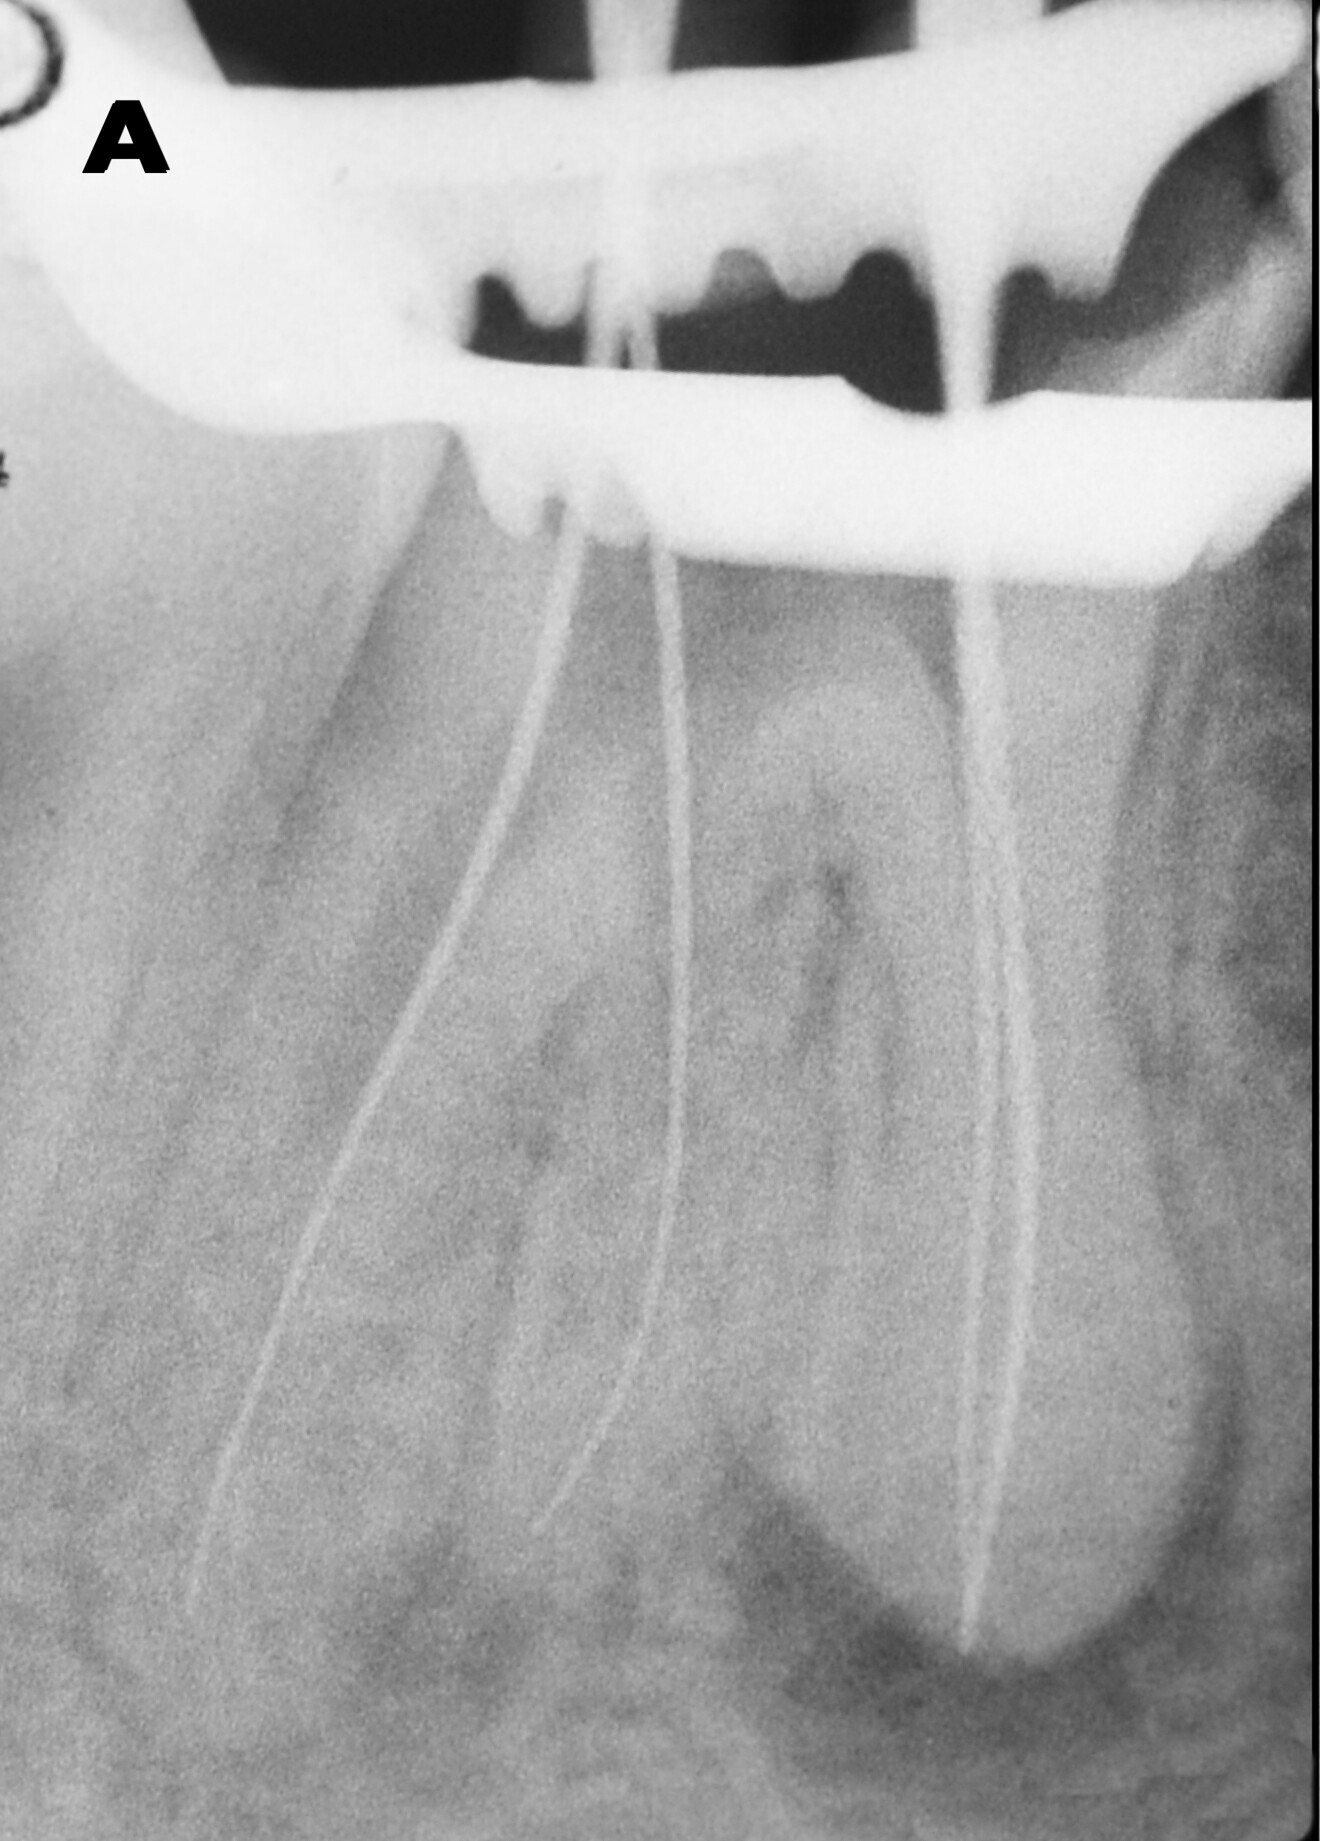

In the radiographic examination, the amalgam restoration showed open margins, especially on the mesial side (Fig. 1). The endodontic treatment was defective: the root canal preparation appeared to have been inadequate, and both the 3D seal and the working length were insufficient. A canal in the distal root seemed not to have undergone any endodontic treatment. Irregular root morphology compatible with hypercementosis was observed in the apical half of the roots of tooth #46, showing an increase of volume of a round shape. A widening of the periodontal space over almost all of its extent could also be observed. A significant apical lesion of the distal root and a smaller one of the mesial root were revealed as well.

The first step was the endodontic reintervention. After local anaesthesia, the operative field was isolated with a dental dam, and a dental dam clamp was placed around tooth #46. The old amalgam was removed, taking care to preserve sound tissue. Once the endodontic filling had been reached, remnants of amalgam and cement were carefully removed. The endodontic filling was removed with rotary instruments for canal shaping and retreatment (ProTaper Universal retreatment files, Dentsply Sirona). The coronal third was treated with the D1 file (30/0.09), the medium third with the D2 file (25/0.08) and the apical third with the D3 file (20/0.07). An entirely mechanical removal procedure was performed to avoid the use of endodontic solvents. The non-treated root canal in the distal root was located and manually prepared with size 15, 20 and 25 K-files. The same files were used for the radiographic check of the working length, which was measured with an apex locator (Fig. 2a).

Fig. 1: Radiograph of the pre-op situation showing insufcient endodontic treatment of tooth #46. Additionally, an amalgam coronal restoration with microleakage was detected. There were also apical lesions evident around both roots. Both neighbouring teeth had migrated towards tooth #46 and closed the interproximal spaces.

Figs. 23a & b: Radiographs before (a) and after (b) treatment, showing dramatic differences. The endodontic treatment had been corrected and the restoration was well adapted and shaped. The interproximal relationships had been re-established through the anatomy of the endocrown. There were no gaps between the restoration and the endodontic filling. The sealing of the endodontic treatment was complete and tight.

Regarding the endodontic retreatment, the preparation and seal of the root canals were appropriate, a suitable 3D seal was achieved and the working length was corrected. Also, the previously untreated root canal in the distal root was properly prepared and sealed (Fig. 23).